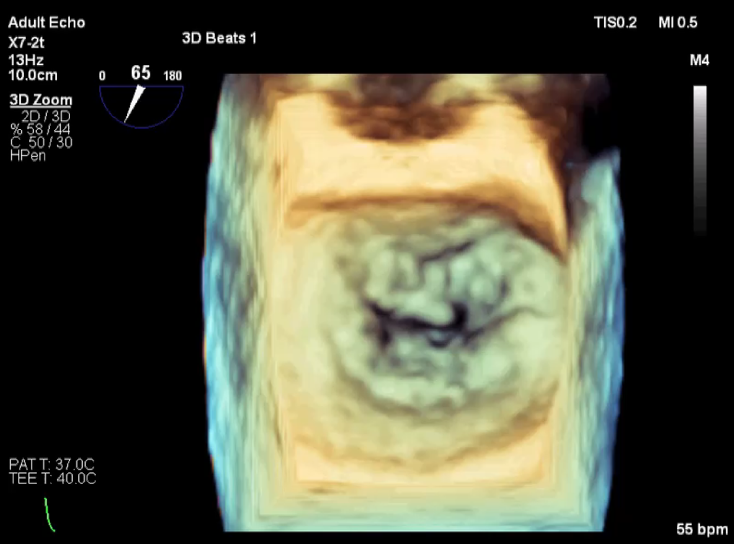

术前超声评估

术前超声诊断

LVOT-color:MR(重度),返流面积11.3cm2

肺静脉血流频谱呈收缩期反向

3D-color MV view:血流主要来源于2、3区

Qlab软件勾画估测瓣口面积约:6.16cm2

TEE LVOT切面返流量评估

TEE 4-Ch view返流量评估